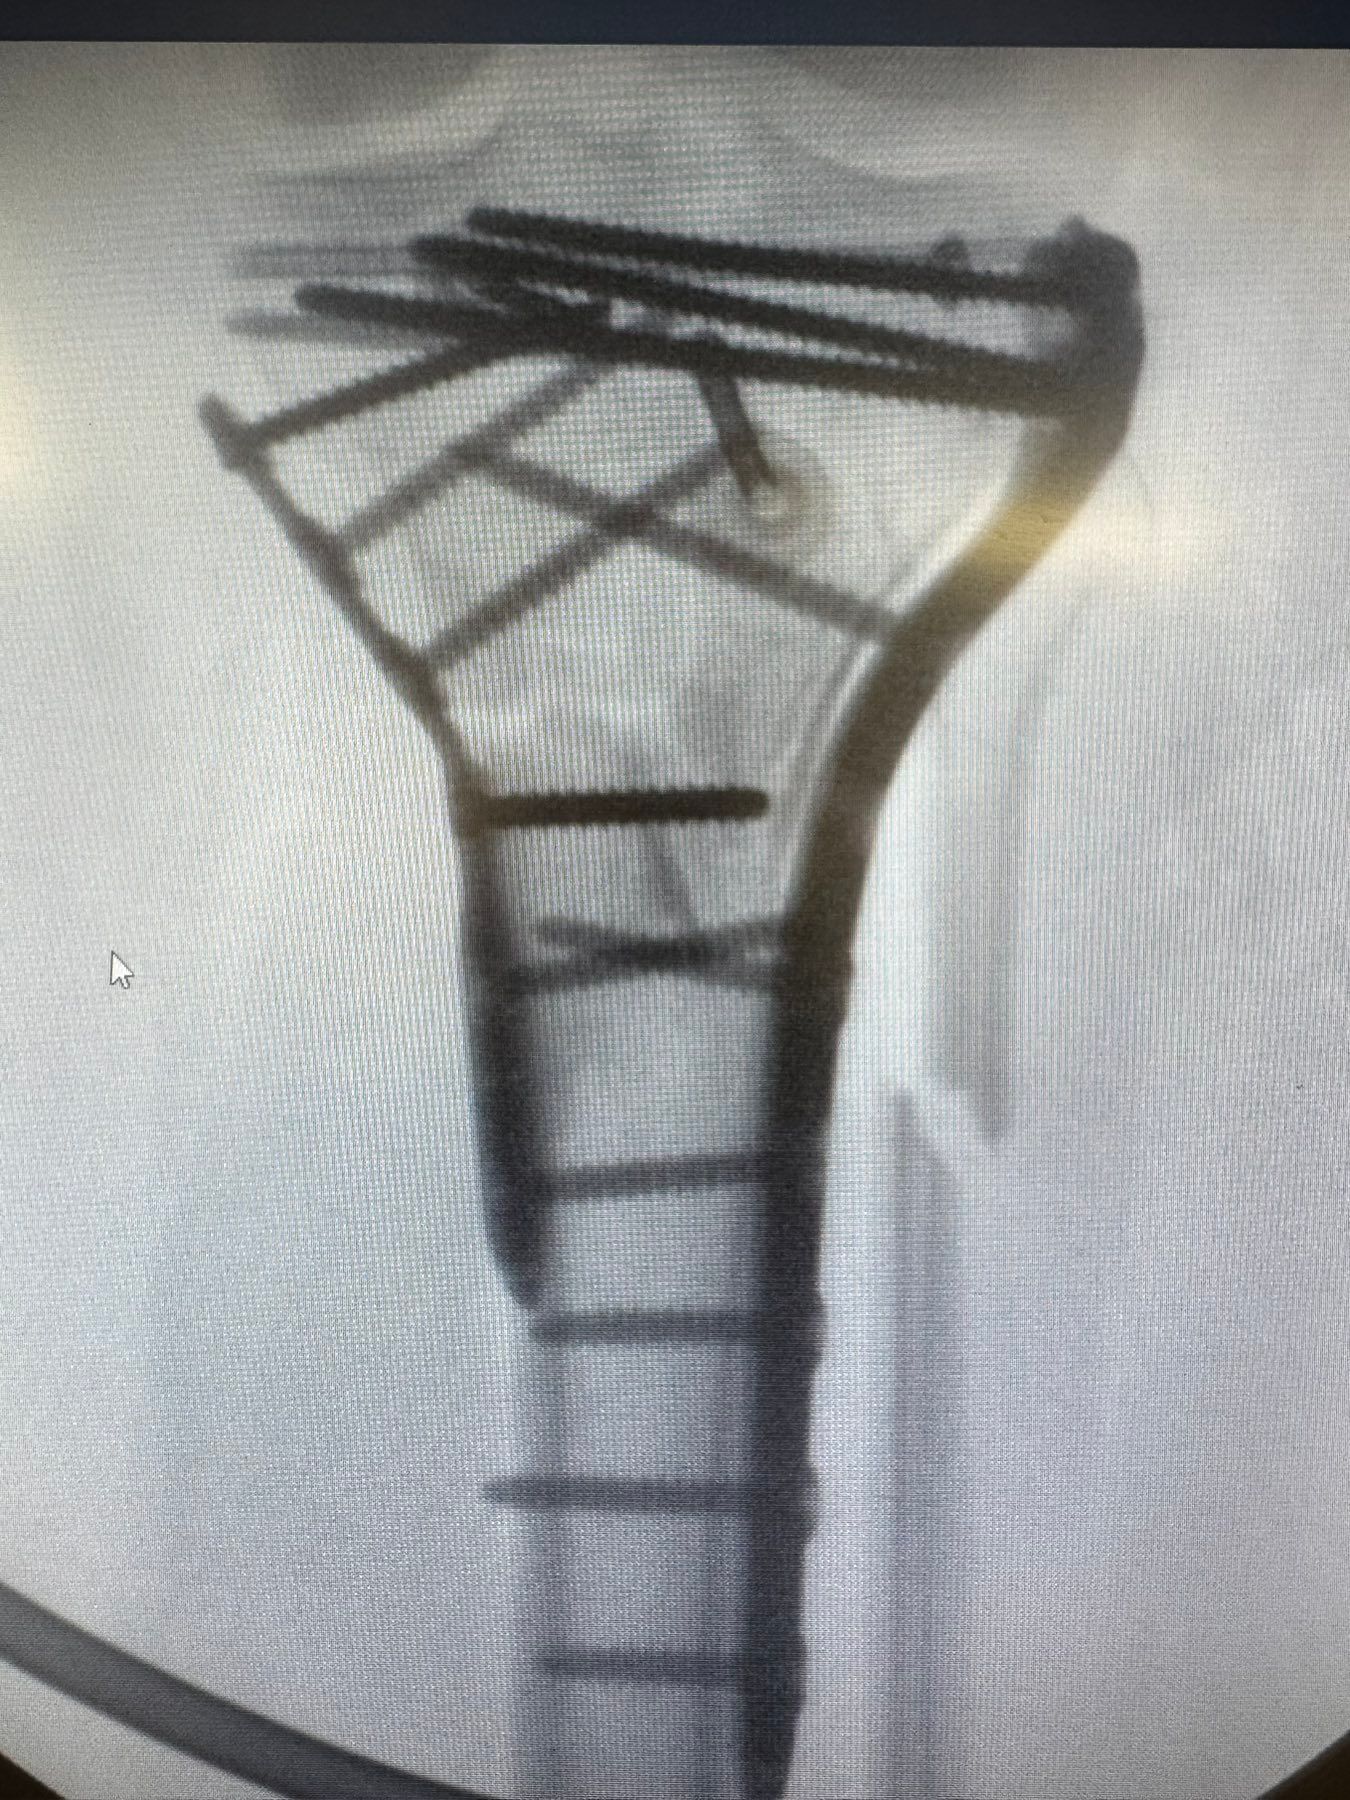

Μετά το χειρουργείο (αποτέλεσμα)